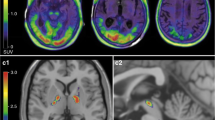

Recently developed molecular imaging approaches now permit the detection of pathological accumulations of Aβ–amyloid plaques [32], and are a subject of several manuscripts in this issue of Clinical and Translational Imaging. PET studies of fibrillary Aβ–amyloid deposition with the thioflavin derivative ligand [11C]Pittsburgh compound-B (PiB) and related clinically-approved radiofluorinated tracers including [18F]Florbetapir, [18F]Florbetaben and [18F]Flutemetamol, reveal important, new biomarker evidence for the role(s) of amyloid deposition in AD and aging (see [33] for review). To summarize the current understanding, Aβ–amyloid deposition is imaged with PET in virtually all patients with autopsy-confirmed AD. The few subjects diagnosed clinically with probable AD with “negative” amyloid scans are believed to be due to clinical misdiagnoses of frontotemporal dementia or of pure DLB as probable AD [30]. Comparative amyloid imaging and pathological confirmatory studies support the image-based classification of individual subject Aβ–amyloid status [34, 35]. The amyloid cascade hypothesis, that extracellular amyloidosis precedes the development of tau-based intracellular NFT pathology in AD, is supported by PiB-PET findings from several investigations. First, the intensity of amyloid deposition does not correlate with the severity of dementia amongst AD patients with “positive” amyloid-PET scans [36]. Second, there is high frequency of AD-range “PiB-positive” findings in pre-AD patients diagnosed with mild cognitive impairment (MCI). Amyloid-positive MCI subjects have very high rates of progression to AD over 3 years [37]. Finally, there is a substantial age-related prevalence of AD-range amyloid tracer binding amongst asymptomatic normal elderly subjects [38–40], and increased risk for development of MCI and AD in these amyloid-positive individuals [41]. These findings in normal elderly and sporadic AD subjects are recapitulated in a recent study of dominant, monogenetic AD. This report indicates the onset of amyloid deposition more than a decade before symptomatic memory deficits, supporting a long asymptomatic lag period between AD-range amyloid deposition and the onset of significant neurodegeneration [42]. Once cognitive impairment and decline develop, there was little further amyloid binding in PET imaging with [18F]Florbetapir. On this construct background, amyloid-PET findings in subjects with synucleinopathy were researched and are summarized below.

A number of prior studies have examined Aβ–amyloid deposition imaging, each involving limited numbers of PD, PDD and DLB subjects [30, 43–60]. Studies employing [11C]PiB predominate in the reported literature. We extracted from the reports the incidence of pathological (AD-range intensity) Aβ–amyloid deposition in these groups (Table 1). Most papers described the numbers of subjects with this intensity range of cortical amyloid tracer binding. However, at least one early publication reported subjects with vs. without any cortical binding above background (see Fig. 2 in [45]). In this case, we revised the authors’ estimates of amyloid incidence by imposing a cutoff threshold of 1.4:1 (cerebral cortex-to-cerebellar cortex ratio), as identified in other studies using this same tracer methodology.

Although there is a wide range of positive Aβ–amyloid incidences and relatively few subjects in most individual studies, there is general agreement that the incidence of AD-range amyloid positivity in PD with normal cognition is very low (individual study range 0–13 %; average 6 %). Within 7 individual reports including cognitively normal, non-parkinsonian subjects, the average incidence of Aβ–amyloid positivity in PD is lower than that in the normals (normal 15 %; PD 6 %). In subjects with PD-MCI, the incidence of Aβ–amyloid positivity ranges between 0 and 11 % (average 8 %), and in 3 of these 4 reports that include also cognitively normal PD groups, the incidence of amyloid positivity is no higher than in PD. Subjects with PDD have higher incidence of Aβ–amyloid positivity than do normals, PD and PD-MCI, ranging from 0 to 80 % in individual reports (average 27 %), while the incidence in DLB ranges between 33 and 100 % in individual reports (average 59 %).

Owing to the small sample sizes in some individual reports, and also potentially to differing image analysis approaches and definitions of AD-range Aβ–amyloid deposition, the individual study ranges within diagnostic groups across studies are relatively broad. However, there is general agreement both within and across virtually all reports on some aspects. First, PD and PD-MCI have similar incidences of Aβ–amyloid positivity, and these are lower than age-comparable normal subjects. Large studies of elderly subjects indicate an average of 30 % of normal subjects between ages 60 and 90 are amyloid-positive [61–63]. Parkinson disease with dementia subjects have higher than normal incidence of amyloid positivity, and DLB subjects have even higher incidence. Dementia with Lewy body subjects, however, demonstrate lower incidence of Aβ–amyloid positivity than do other large studies of probable Alzheimer disease [36, 40, 41, 43, 53, 63].